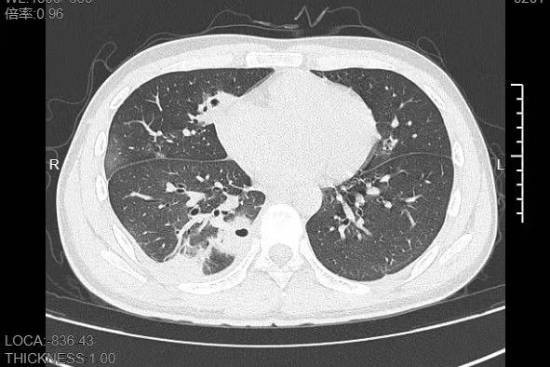

熬到第三天,小林已经烧到39℃,赶紧来到宁波大学附属第一医院就诊。接诊的丁群力主任医师一看他的症状,立刻安排了CT检查。结果显示:小林的肺里有十几个空洞,部分肺组织已经坏死,这是典型的血源性肺脓肿。